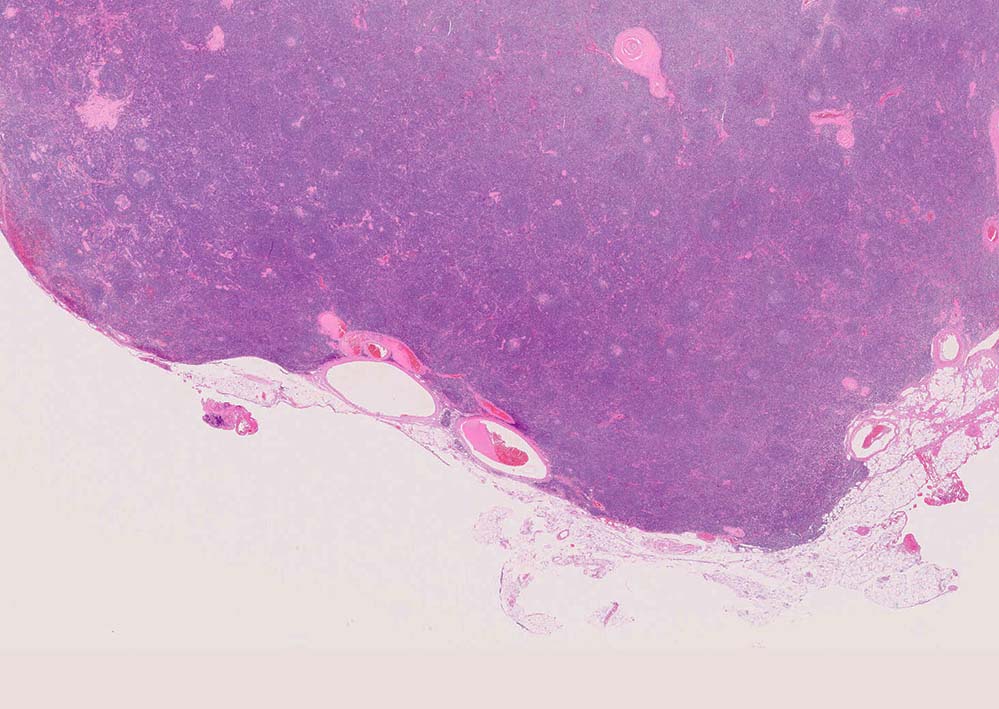

Castleman diseaseの病理

局所型CDの90%はHV type, 10%がPC type.

硝子血管型 hyaline vascular type: 臨床症状に関係なく3つの病理組織所見で診断が決まる。*1

1. 萎縮した胚中心をもつ異常な血管増生を示すリンパ濾胞(Lolli-pop follicles. Lolli-popはキャンディ-の名前のようです)

2. 濾胞間リンパ組織の線維化, 血管増生

3. 被膜は肥厚し, 少なくとも病変中心部ではsinuses(リンパ洞)を欠いている

「広いmantle zoneの取り巻いたリンパ球の少ないFDCのめだつ小さな濾胞, 硝子化することもある, 濾胞間は細血管でいっぱい」がkey word